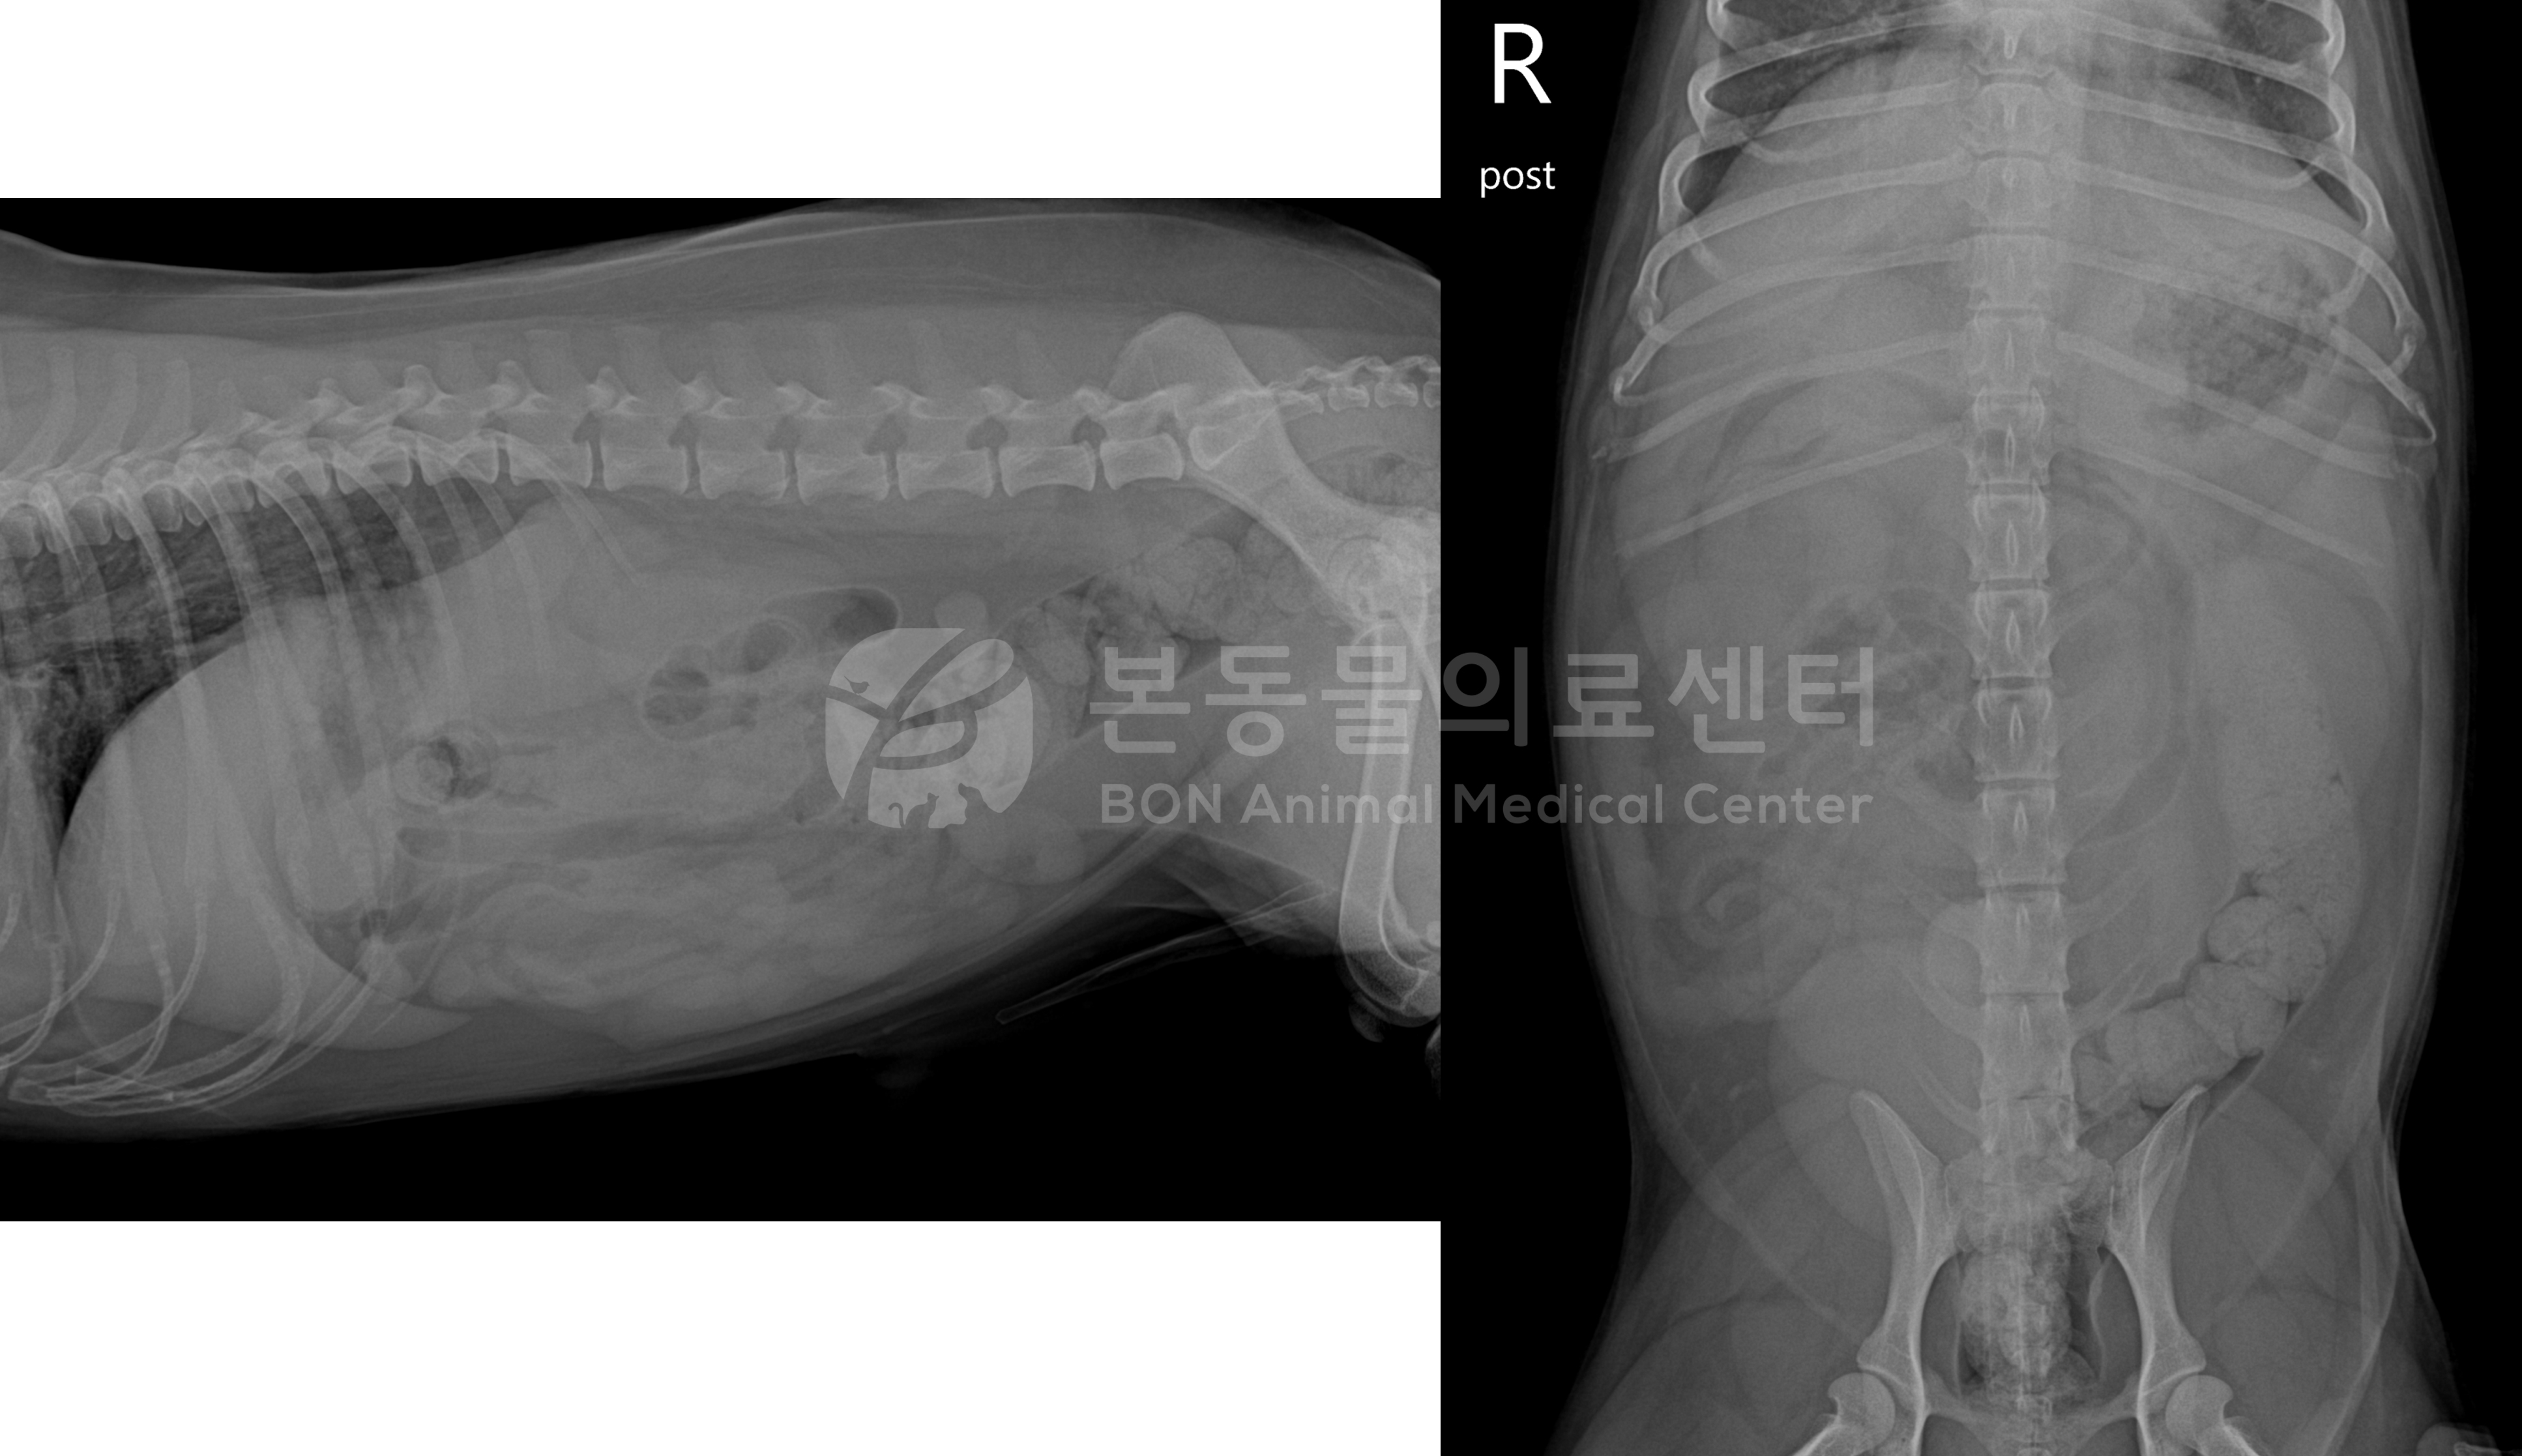

다행히 환자는 1회 구토에 바로 위 내 저류된 씨앗이 확인되어 이 후 위장관 보호제 처방하여 귀가하게 된 케이스이다.